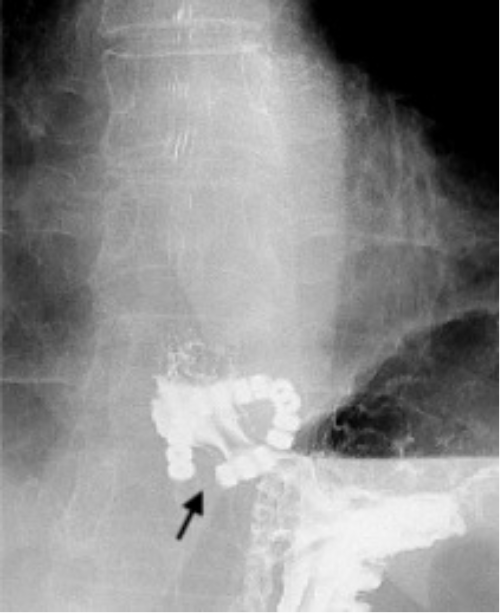

The patient was referred to our institution for a second opinion on her dysphagia five years after device implantation. At her presentation, she reported difficulty swallowing with all food consistencies. We performed a comprehensive workup to investigate the etiology. Barium esophagram revealed delayed esophageal emptying and a concerning finding—dissociation of the posterior beads of the LINX system (Figure 1). This dissociation was not documented on prior studies, although image comparison was limited due to unavailability. High-resolution manometry (HRM) demonstrated persistent issues despite a previous repair attempt. Despite 100% bolus clearance, the test showed weak esophageal peristalsis and a recurrent 2 cm hiatal hernia. There was no device erosion or malposition on EGD.

Figure 1. Barium Esophagram. Published with Permission

A.

Illustrating discontinuity in the posterior section of the LINX device during contrast passage. A) Pre-contrast image shows the LINX device in its intact state

Illustrating discontinuity in the posterior section of the LINX device during contrast passage.  B) Following contrast passage through the device, separation is evident between the posterior beads (indicated by arrow).